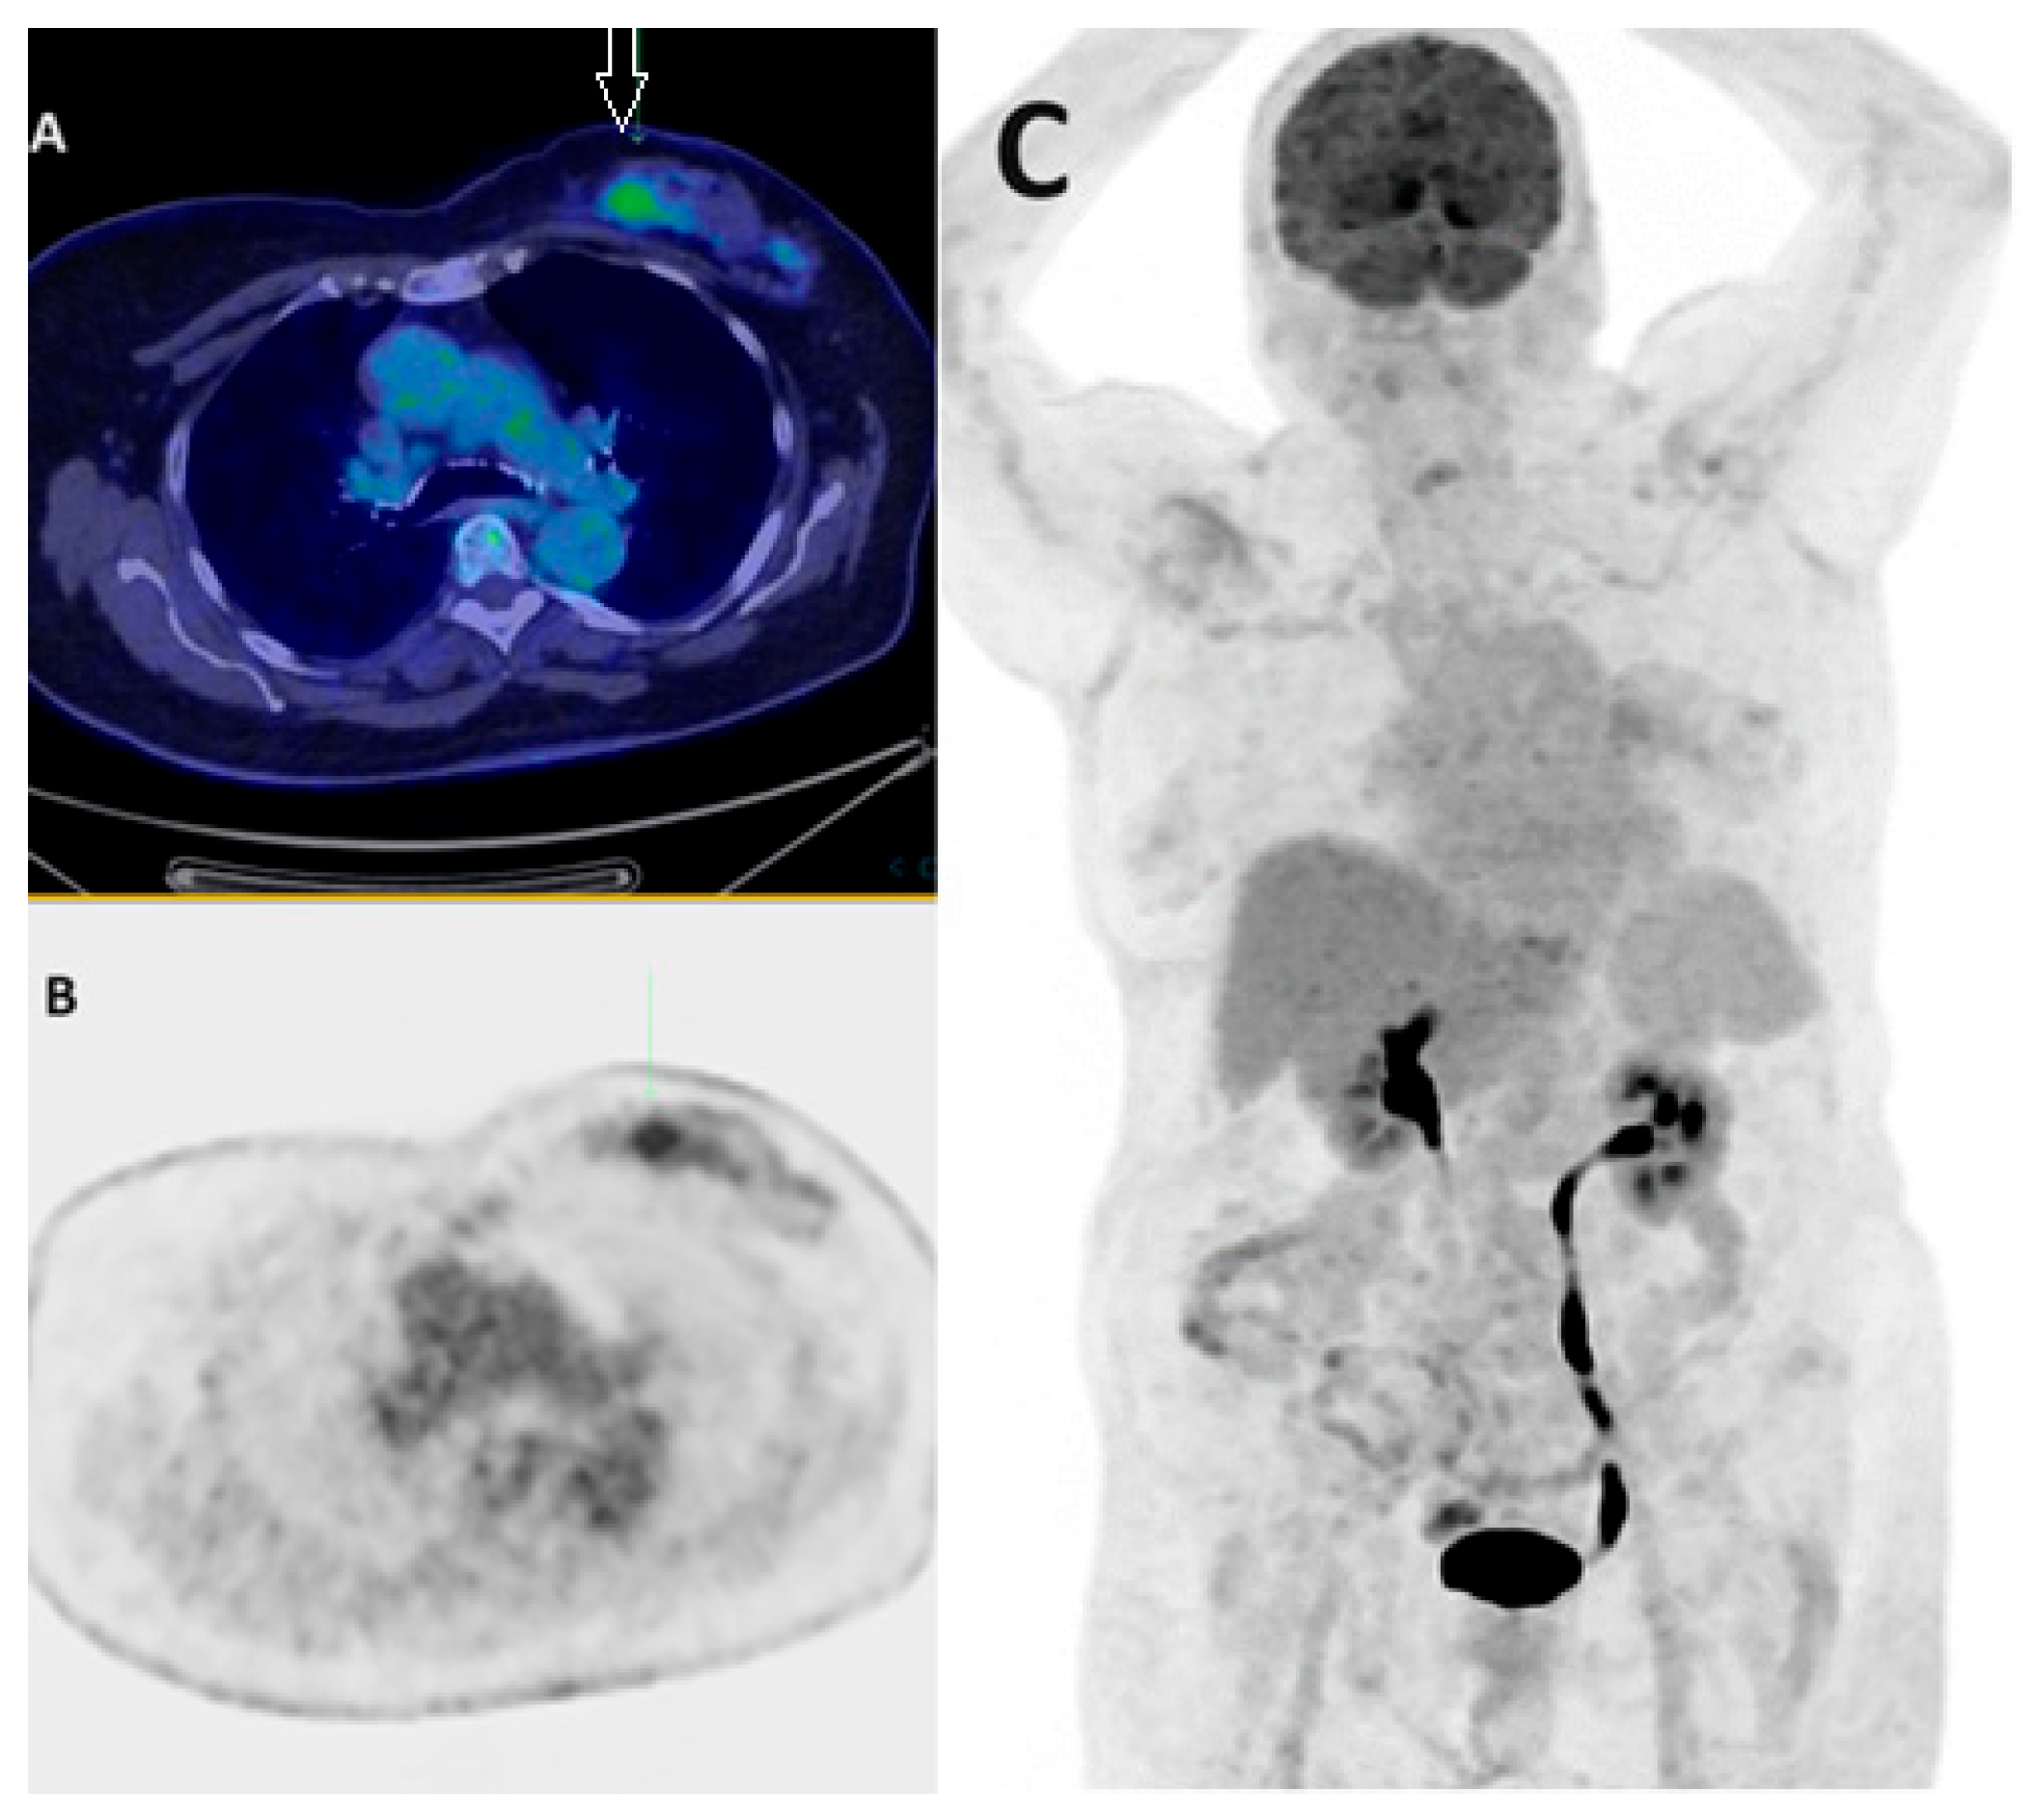

- Kömek, H.; Can, C.; Güzel, Y.; Oruç, Z.; Gündoğan, C.; Yildirim, Ö.A.; Kaplan, I.; Erdur, E.; Yıldırım, M.S.; Çakabay, B. 68Ga-FAPI-04 PET/CT, a new step in breast cancer imaging: A comparative pilot study with the 18F-FDG PET/CT. Ann. Nucl. Med. 2021, 35, 744–752. [Google Scholar] [CrossRef] [PubMed]

- Elboga, U.; Sahin, E.; Kus, T.; Cayirli, Y.B.; Aktas, G.; Uzun, E.; Cinkir, H.Y.; Teker, F.; Sever, O.N.; Aytekin, A.; et al. Superiority of 68Ga-FAPI PET/CT scan in detecting additional lesions compared to 18FDG PET/CT scan in breast cancer. Ann. Nucl. Med. 2021, 35, 1321–1331. [Google Scholar] [CrossRef] [PubMed]